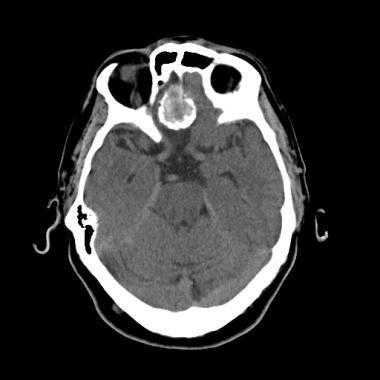

Псаммоматозная менингиома. КТ-исследование кальцифицированного объемного образования, обнаруженного на рентгеновском снимке. На томограмме, полученной на уровне верхней границы орбит, видна опухоль в области решетчатой пластинки (в области ольфакторной ямки).